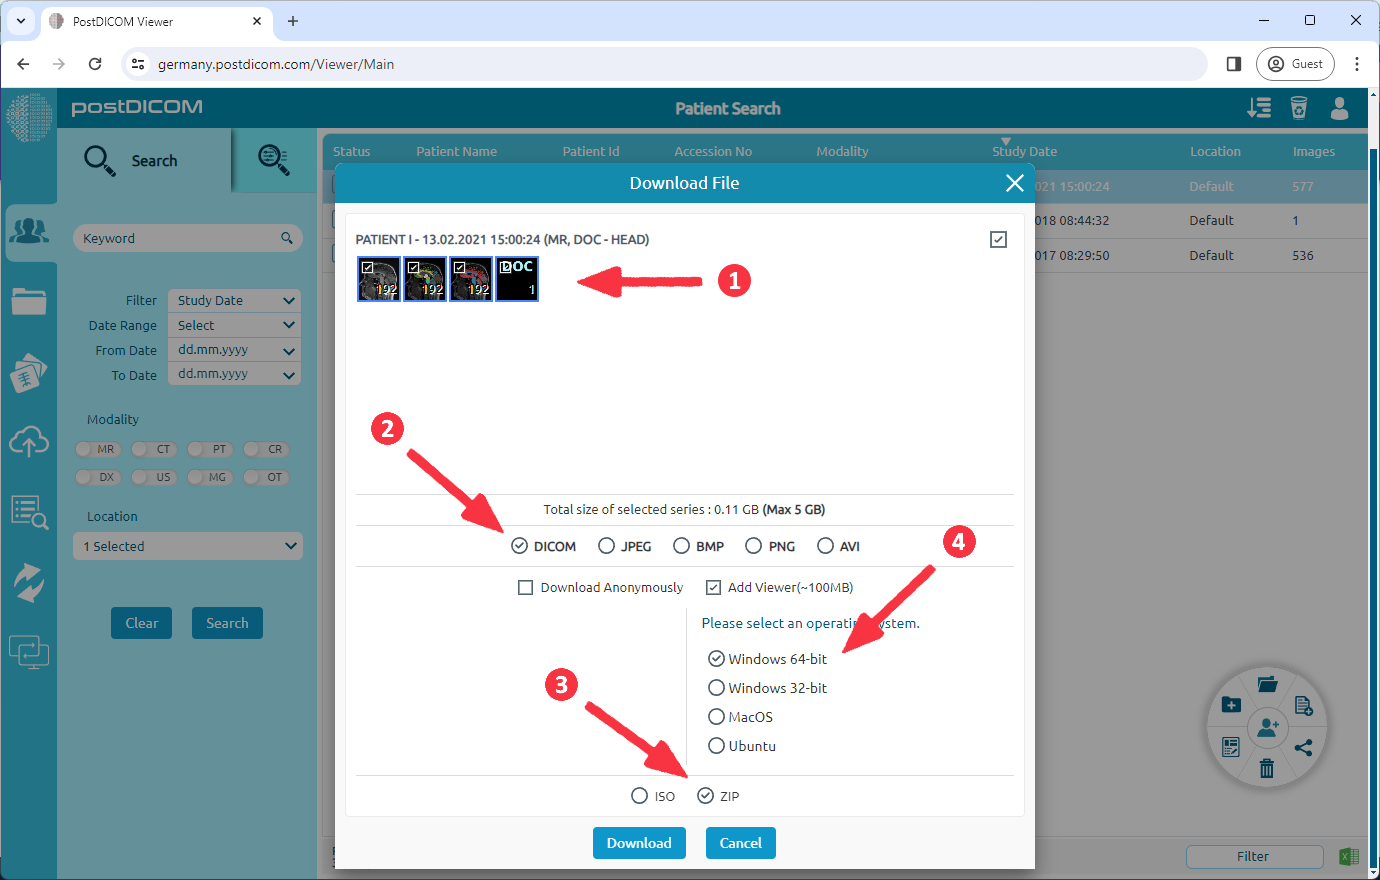

(1) Select the series to be downloaded. (2) Select 'DICOM' format. (3) Select 'ZIP' format you want to download. (4) To add a viewer, you should select the 'Add Viewer' option and select the Windows operating system with system type(x64 or x32). This option adds the 'PostDICOMCDViewer' application, which is approximately 100 MB in size. Finally, click the 'Download' button.